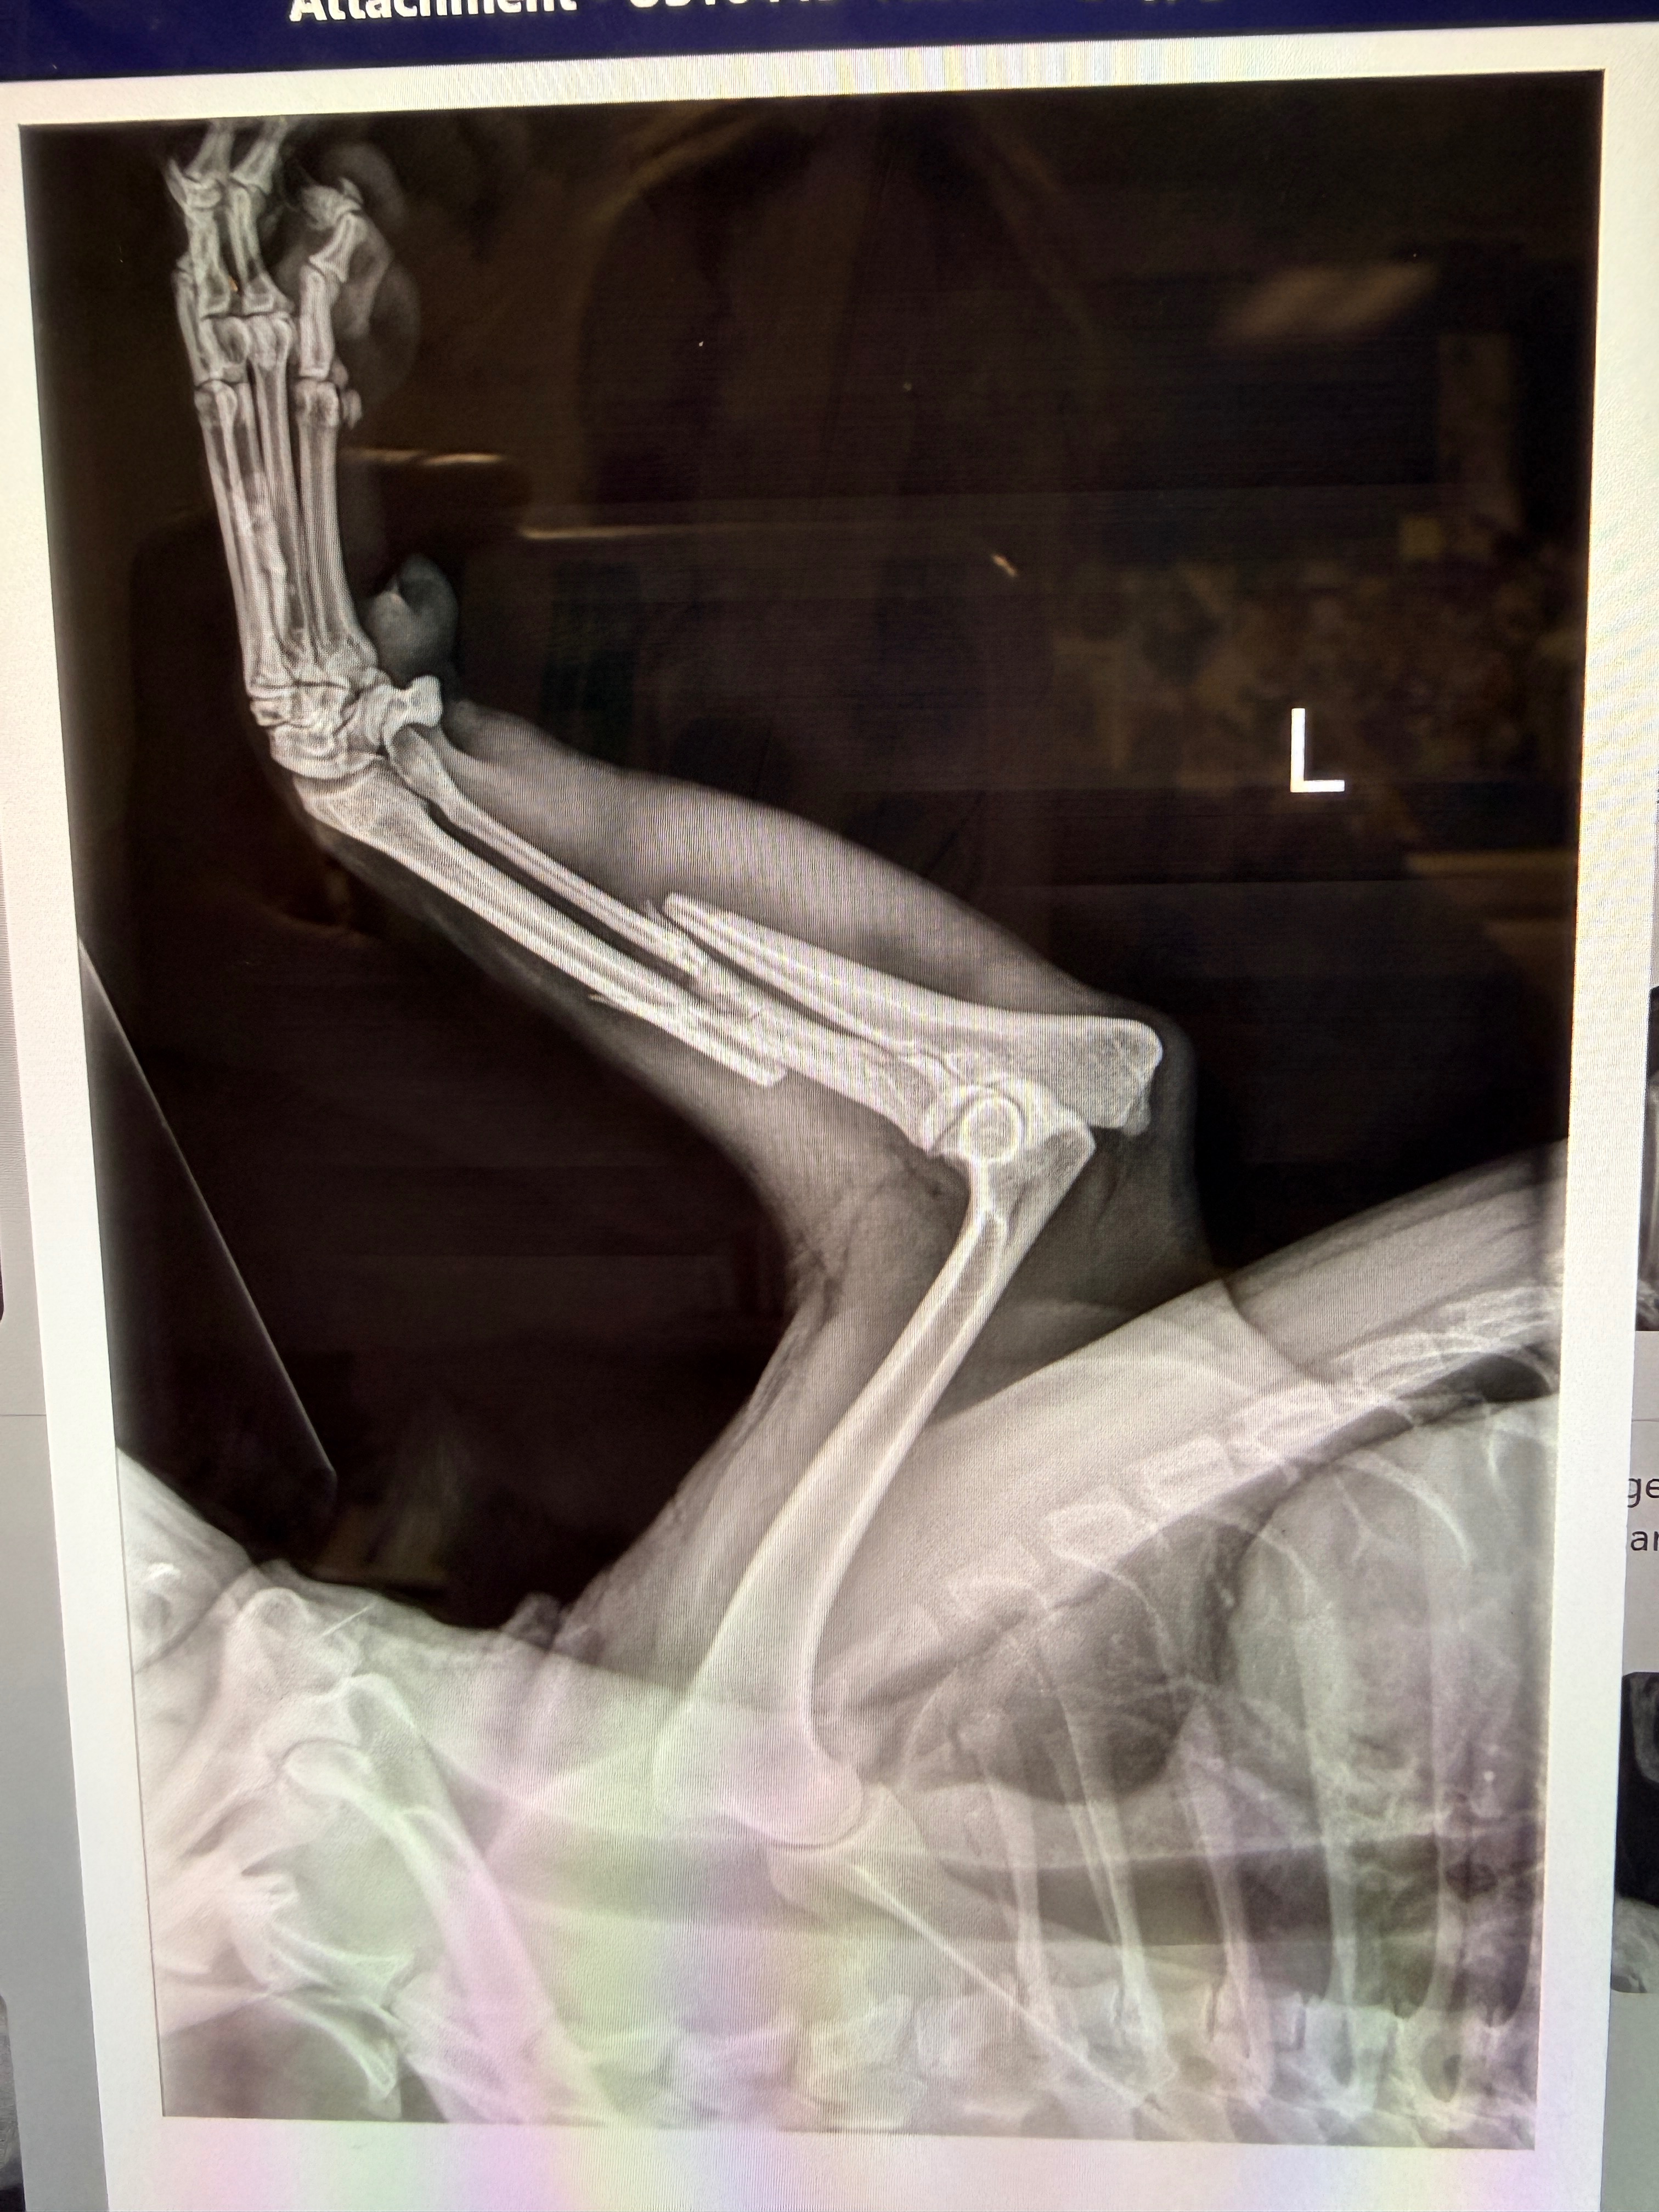

Hi there, my name is Tessa! I want to introduce you to Kevin. Kevin is approximately a 1 year old, Shiba Inu/cattle dog mix. The sweetest boy in dire need of surgery. Kevin was brought into the animal hospital I work at by a good sam when he was hit by a car. We searched for his family by posting on nextdoor, facebook groups, pawboost and Petco lost/found. No one has come forward and Kevin desperately needs this surgery to go to a rescue. Rescue’s can’t afford another medical case. Which is where I need your help! Kevin has a broken front left leg and a proximal tibial fracture and a medial collateral ligament of the left stifle. We can fix him and give him the life he deserves but we need your help! Whether you donate money or know of a rescue/foster please let me know!